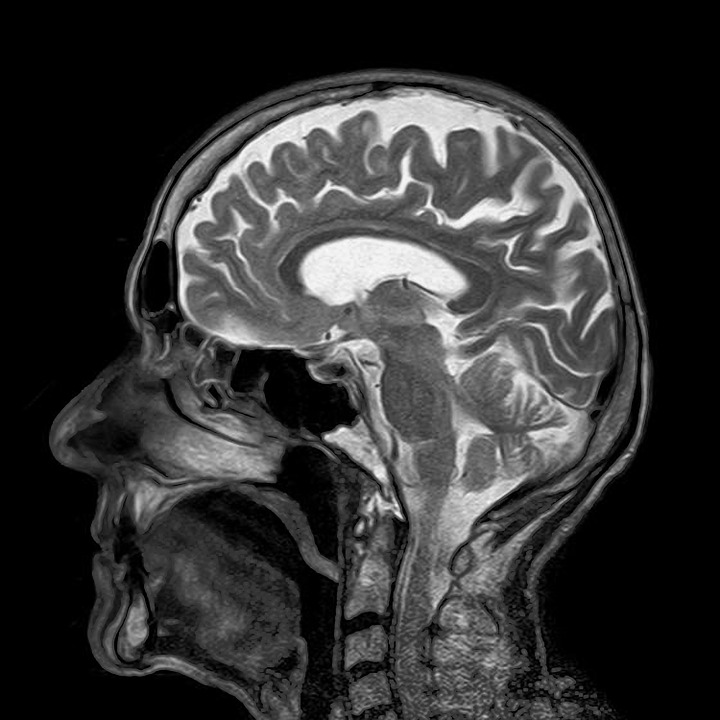

MRI是一种看着身体内部而不将其切开的方式。好吧,这就是X射线和超声波的作用,但是MRIS比他们中的任何一个都要凉爽。我们可以在一个人的内部看着一个人,而无需危险的波浪,我们可以在工作状态下看到所有这些,而无需手术。我们可以在MRI的帮助下查看大脑中的神经功能以及流经静脉的血液。MRI扫描可以轻松检测任何异常,然后可以相应治疗患者。但这不是为什么您在这里,您在这里看到Mris Go Go Gererk,我们会给您的。首先需要进行一些工程评论!

如您所知,我们的身体是70%的水。由于我们体内存在的水是溶液的形式,因此可以很容易地将其离子化。因此,强磁场可以对齐我们体内的大多数分子。MRI中的磁铁比普通的家用冰箱强20倍,它引起了我们身体周围的磁场的共鸣。扫描仪扫描了这种磁力,然后将其下面的区域插入。这是一件非常酷的医学工程,但是是的,如何吹牛?